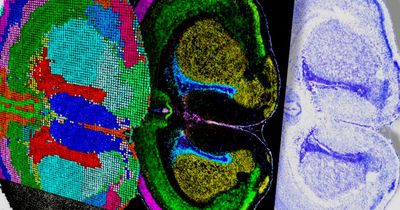

Новый инструмент считывает химические сигналы мозга в режиме реального времени

Нейробиологи из США синтезировали новый белок, способный обнаруживать высвобождение глутамата, основного возбуждающего нейромедиатора мозга, с чувствительностью на уровне отдельных везикул. Этот прорыв позволит исследователям наблюдать за взаимодействиями клеток мозга в режиме реального времени и регистрировать химические сигналы, которые до сих пор оставались незаметными. Разработка обещает ускорить исследования неврологических расстройств, включая болезнь Альцгеймера, шизофрению, аутизм и эпил